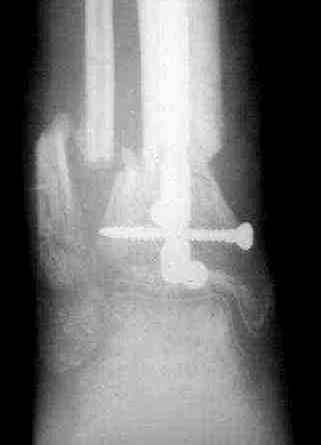

7, 8, 9, 10, 11 - через 8 мес после травмы перелом сросся.

Пациент ходит без дополнительной опоры, не хромает (видеоролик выложил сюда